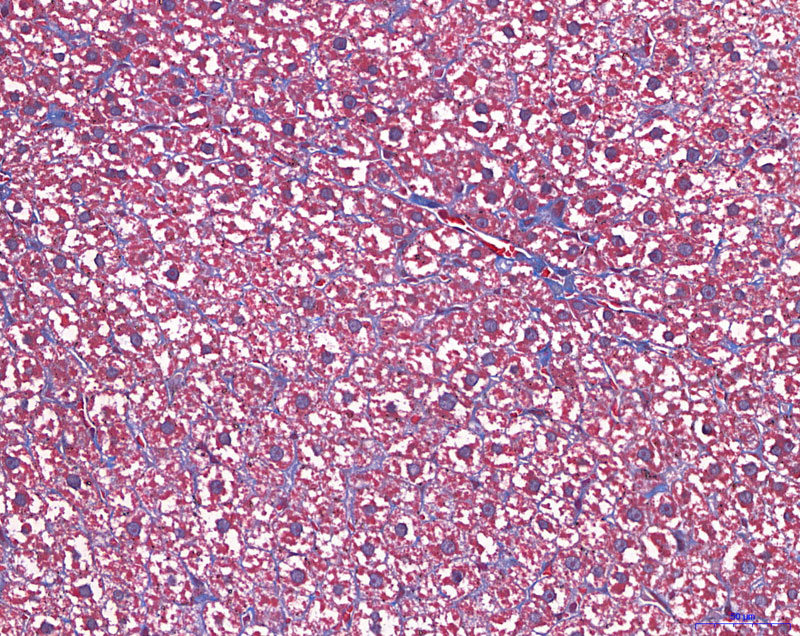

MASSON染色【組織病理染色】

給藥組-400

模型組-400

正常組-400